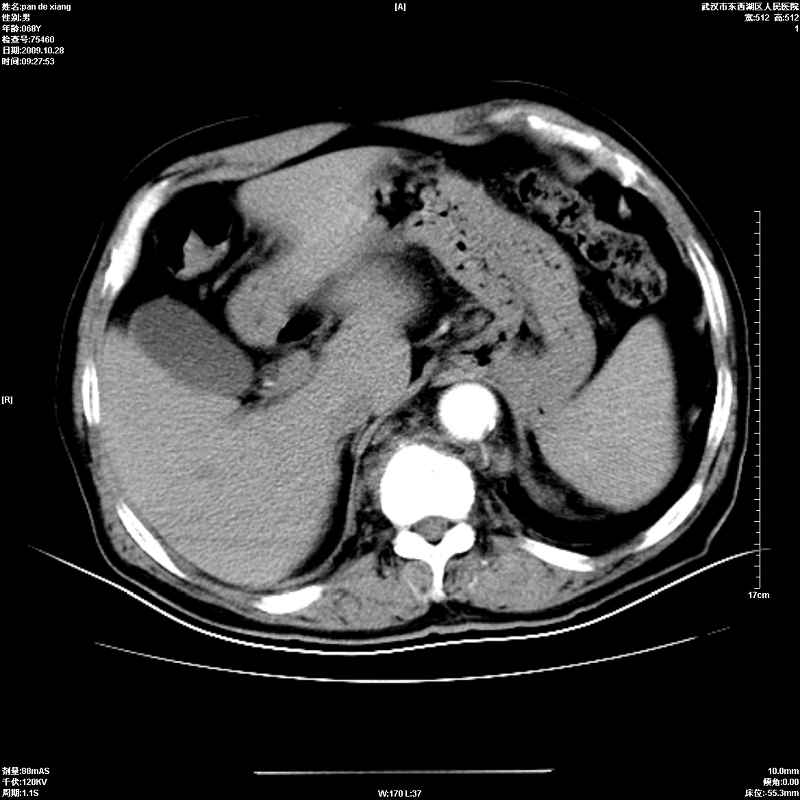

以下是引用杀毒软件在2009-10-28 20:41:00的发言:[br]结合临床考虑---白血病双肾改变或淋巴瘤。

以下是引用zxl51642在2009-10-29 9:59:00的发言:[br]结合临床“单克隆免疫球蛋白血症”,考虑双肾为继发损害并肾功能不全(尿中大量igg及少量iga、igm等大分子免疫球蛋白滤出所致继发损害),椎前软组织肿块为髓外造血。与浆细胞瘤有区别,平扫时有战友说的很清楚。